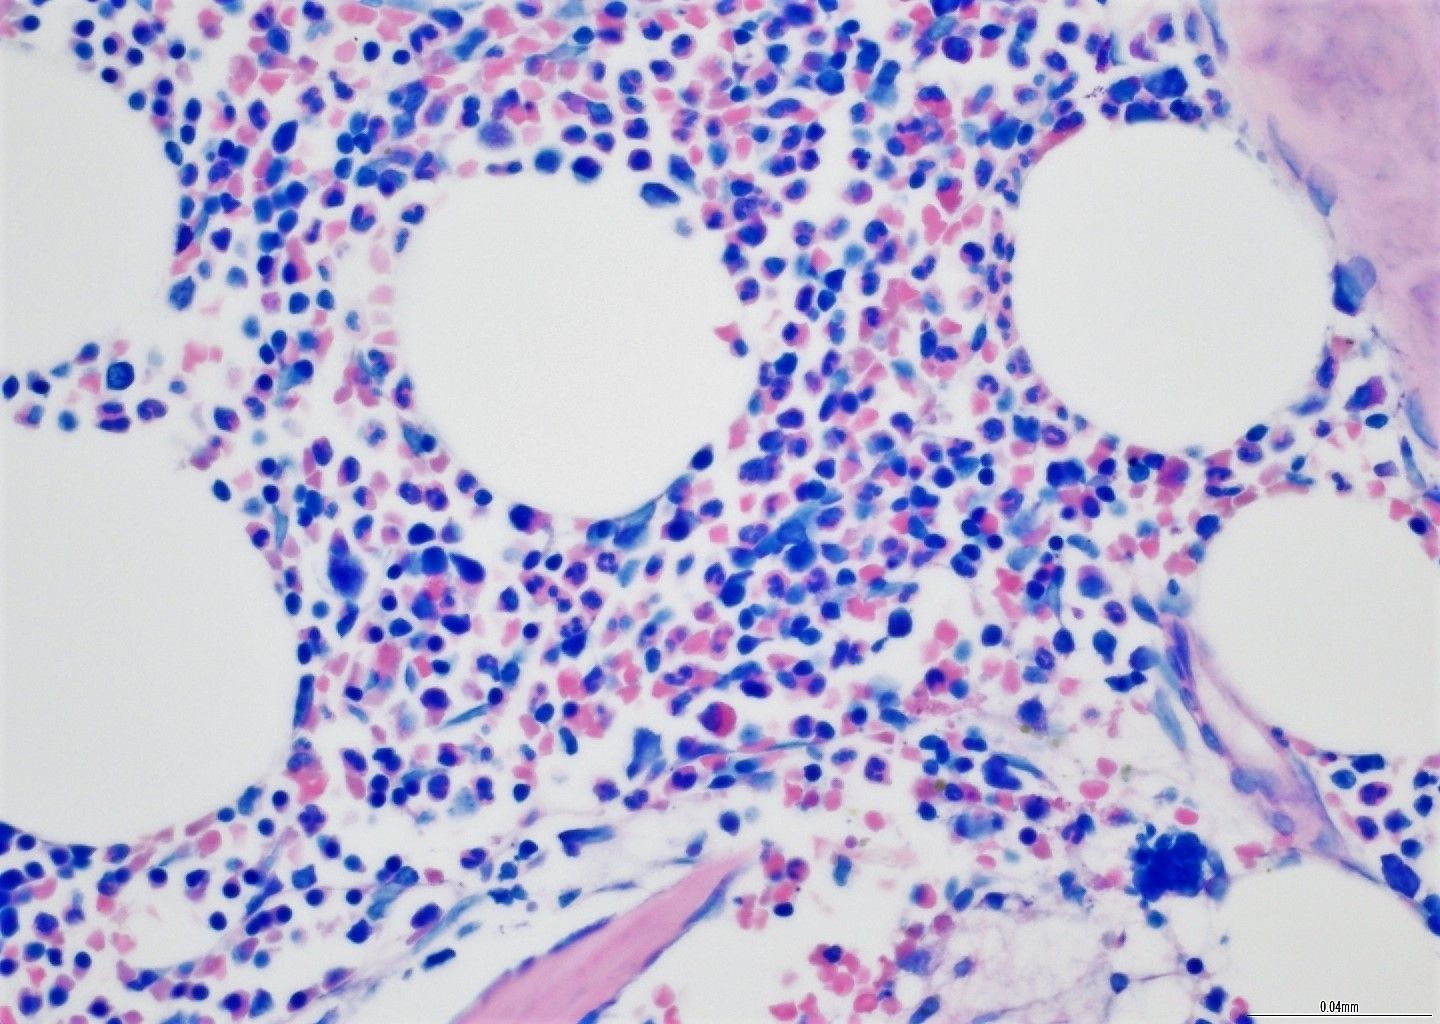

- Demonstration af specifikke blodcellemål i BMT-biopsien